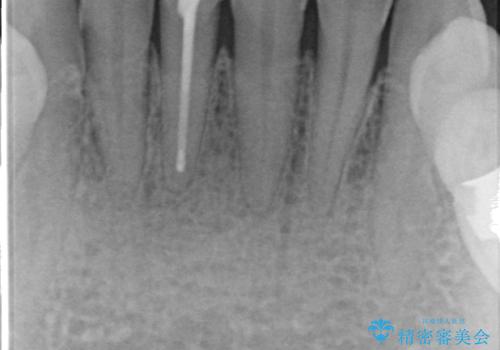

- 下顎前歯の見た目が気になるといらっしゃった方の症例です。

右下1の再根管治療終了後、オールセラミッククラウン(スペシャル)による補綴を行いました。